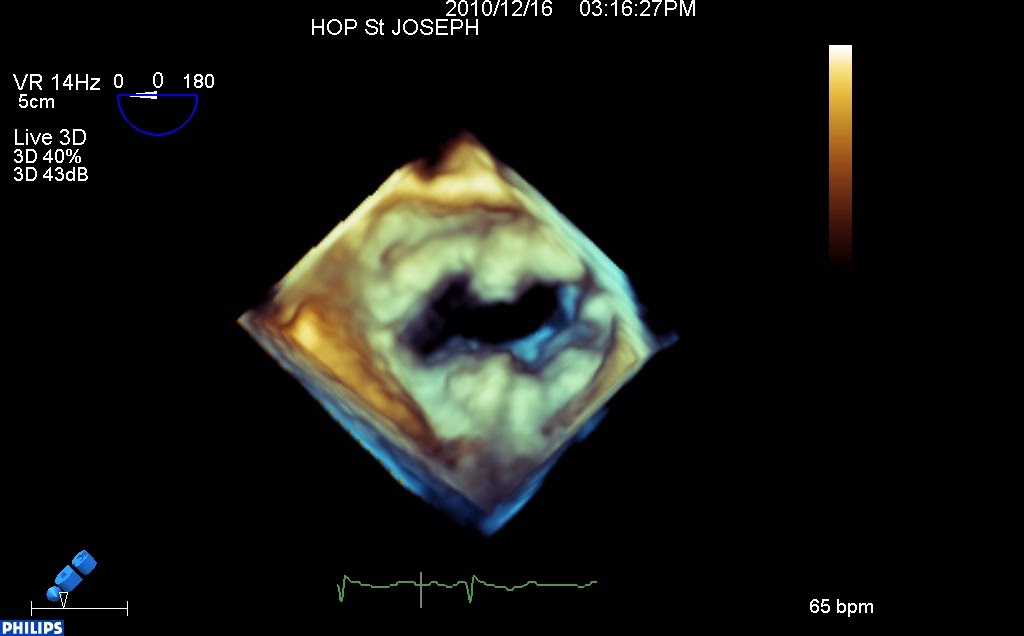

Valve ouverte :

Valve fermée (enfin presque, car le P3 et son cordage prolabent)

On distingue toujours le prolapsus de P3 (cette fois à droite de l’écran, sur cette vue « chirurgicale » de la mitrale : auricule à droite, aorte en haut, commissure postérieure à droite de l’écran). Mais on prend la mesure de l’énorme calcification de l’anneau mitrale, quasi circonférentielle, qui ne paraissait pas franchement évidente en 2D…